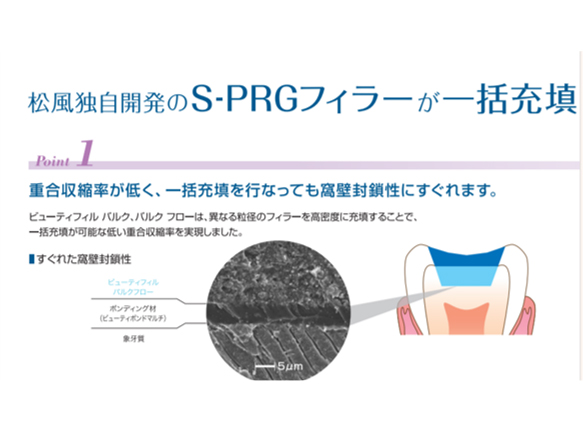

POINT接着技術の特徴を生かした充填技術、覆髄技術

歯髄保護とは、歯の神経組織を保存する医療行為です。むし歯が進行して激痛を伴う場合、神経除去の必要性が高まります。ただし、むし歯の状況次第で神経を温存できる場合もあります。具体的には、むし歯部を削り、薬剤で穴を埋め神経を保護する方法です。これが歯髄保護です。歯髄保護には、直接法と間接法の二種があり、むし歯の程度で処置が変わります。

むし歯になっても、初期のむし歯であれば型取りをしないCR修復(コンポジットレジン修復)を行うことが可能です。

削った箇所に、光に反応して硬化する歯科用プラスチックを入れるため、治療期間が短く済むケースがほとんどです。また金属とは違い、歯の色に近づけたり、柔軟性があるため歯に負担が少なく自然な仕上がりになります。